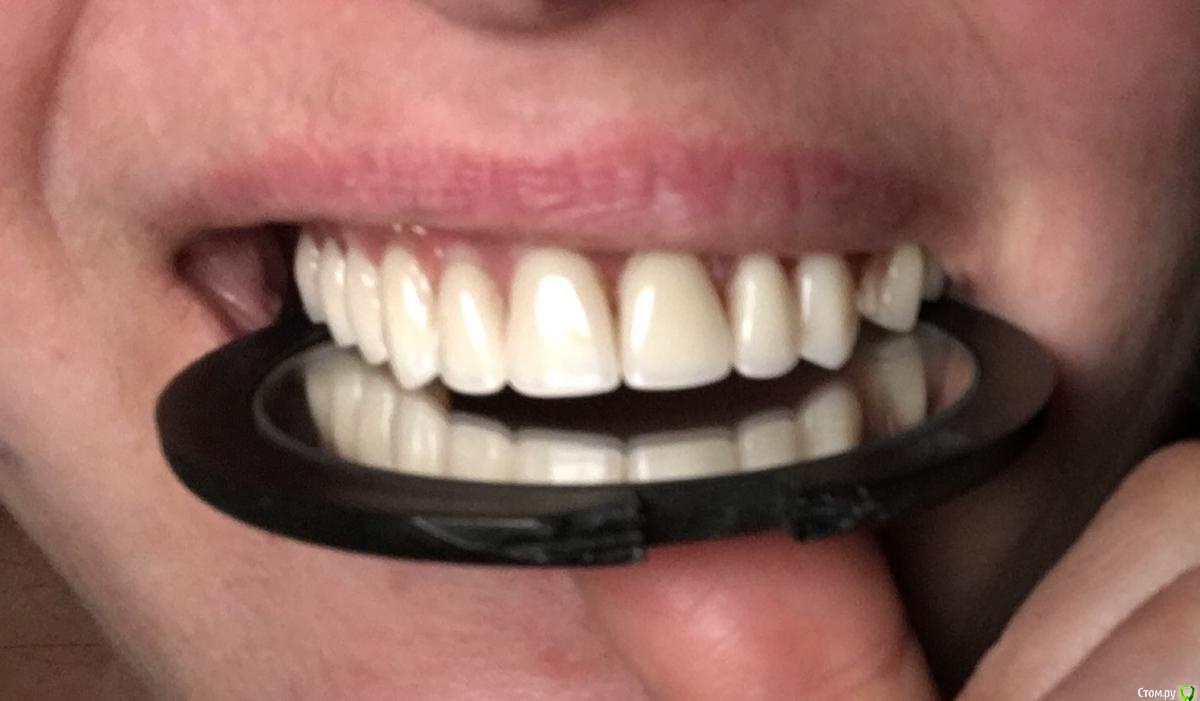

Maggie78rus Опубликовано 20 марта, 2017 Автор Поделиться Опубликовано 20 марта, 2017 (изменено) https://drive.google.com/open?id=0B5M5deCMkPdRdExpV1RRdTRGZ3MВот, присоединила некоторые фотографии. Прошу извинить за демонстрируемый кошмар, поверьте, мне ещё и больно плюс я не могу держать равновесие Разыскиваю хорошего ортопеда в Санкт-Петербурге. Слышала много вариантов лечения вплоть до ортогнатологической операции и переделки конструкции заново на других имплантатах. Изменено 20 марта, 2017 пользователем Maggie78rus Ссылка на комментарий

Maggie78rus Опубликовано 20 марта, 2017 Автор Поделиться Опубликовано 20 марта, 2017 ортопед это и есть "протезист" Ортодонт вам не нужен. Зубов то нет. Честно говоря данных мало. Почему надо ставить зигомы не ясно.Мне тоже не совсем ясно, зачем мне удалили одни имплантаты и поставили на другие протез с такой же окклюзией. Все, конечно, путается в голове от этого нескончаемого кошмара и , извините, зубной боли, хотя зубов уже 2 года нет- потеряла после первого протезирования. Очень устала.Проблему с окклюзией, я получила 8 лет назад.Тогда я ничего не могла сделать, не могу сделать ничего и сейчас. Какое-то дежавю: милые стоматологи встречают меня с распростертыми объятиями, берут деньги, потом у них ничего не получается, т.к. все снимали анатомические слепки и по ним отливали мосты, а теперь протез... Никто не пользовался артикулятором и лицевой дугой. Я приходила к врачам, надеясь получить качественную стоматологическую помощь. Для установки скуловых имплантатов мне даже обещали использовать высокие шведские технологии трёхмерного моделирования... но, погрузив меня в медикаментозный сон, опять сняли оттиск и отлили протез по образу и подобию того, что я так стремилась исправить: страшного, маленького, заваленного то на один, то на другой бок.И так три раза. У меня отваливался то передний зуб, то клык...ничто не убеждало врача сделать дугу об'емнее...в конце-концов я настояла на диагностике у гнатолога, но диагностические модели разбили в окклюдаторе.В Клинике все врачи -специалисты широкого профиля да ещё и лекции читают, но мне-то они помочь не могут и не хотят: они уже получили все деньги, извините, обманом, а у меня ещё не стоит временный протез с нормальной окклюзией.Что делать? Ума не приложу! То, что зубов нет и ты не чувствуешь, как идёт нагрузка от зубов, думаю, неправда. Чувствуешь. Чувствуешь, как нёбный шов уходит в сторону...Попросила собрать консилиум врачей, чтобы помочь советами - результат один- делают оттиск, потом делают вид, что моделируют на воске, иногда получается здорово! Но потом ставят все тот же оттиск, но под другим углом Ссылка на комментарий

Maggie78rus Опубликовано 30 марта, 2017 Автор Поделиться Опубликовано 30 марта, 2017 Состоявшая "дискуссия" лишний раз подтвердила, что Зигомам пациентам надо сказать НЕТ. Проблем они не решают, а лишь добавляют, особенно тяжело установить на них грамотную ортопедическую конструкцию: несмотря на то, что методика имплантации авторская и требует предварительной диагностики, четкого планирования и соблюдения Протокола проведения операции, недобросовестные хирурги вносят свое НОУ-ХАУ и превращают имплантат с пожизненной мировой гарантией в железяку, на которую гарантия вообще не распространяется и протез не устанавливается. Особенно хочется предостеречь всех желающих получить голливудскую улыбку от врача, который ГАРАНТИРУЕТ ее вам, просит заплатить в карман, не ведет медицинской документации... Ссылка на комментарий